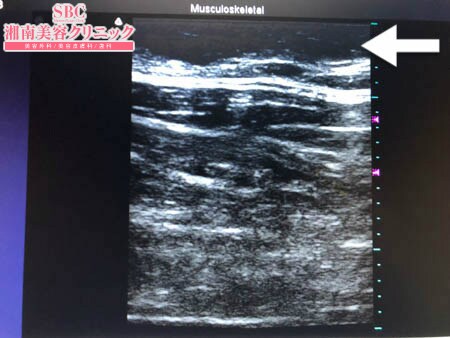

No.236361【脂肪吸引】【動画あり】湘南美容外科全ドクターの脂肪吸引最高責任者である竹田先生による脂肪吸引のフォトギャラリー!「関西からご来院された患者様の太ももの脂肪吸引!」術中3Dタッチビュー・左太もも前面